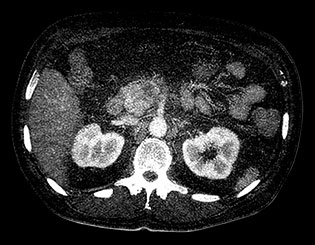

Obraz MonoE

Na tym zdjęciu pokazano zsyntetyzowany obraz monoenergetyczny uzyskany przy wstępnie ustawionej wartości keV.